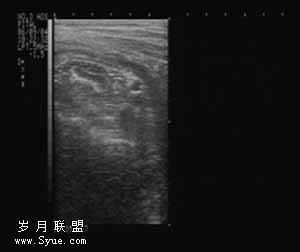

2.2.1 单纯性阑尾炎 壁较完整,连续性好,呈“双边影”,厚约0.15~0.2cm,体积相对较小,阑尾横径约在1.0cm左右,阑尾腔内低回声较均匀(如图1)。

图1